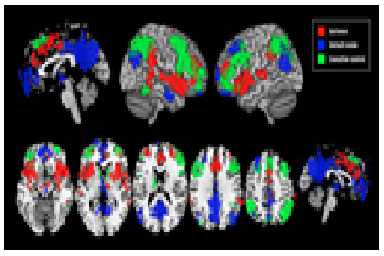

Funkcionālās atšķirības smadzeņu savienojamībā var izskaidrot kāpēc daži indivīdi ir mazāk vai vairāk hipnotizējami, secināts pētījumā, publicētā Archives of General Psychiatry oktobra izdevumā. Fumiko Hoeft, M.D., Ph.D, no Stanford University School of Medicine in California un kolēģi veica neiro...